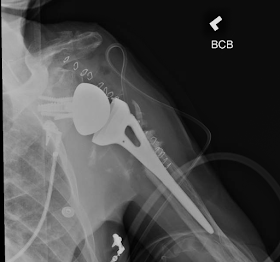

The preoperative and postoperative images are shown below. This patient is in his 80s.

The use of the reverse shoulder arthroplasty in the elderly is valuable not only for the treatment of rotator cuff arthropathy but also for the treatment of painful non union of the proximal humerus. My experience has been that open reduction and internal fixation is not a predictable solution in these cases due to the osteoporosis, poor nutrition and blow flow to the bone. This case below illustrates that the reverse total shoulder replacement provides solutions for problems that we did not have a solution before.

I prefer to use large glenospheres for those cases as instability can be a problem

I also prefer to use eccentric glenospheres which minimize the risk of impingement and scapular notching especially when the neck shaft angle of the humeral stem is more than 135 degrees. Those stems bring the humerus closer to the glenoid and can impinge. Impingement can be avoided by implanting a glenosphere with a 2-3 mm of inferior eccentricity.